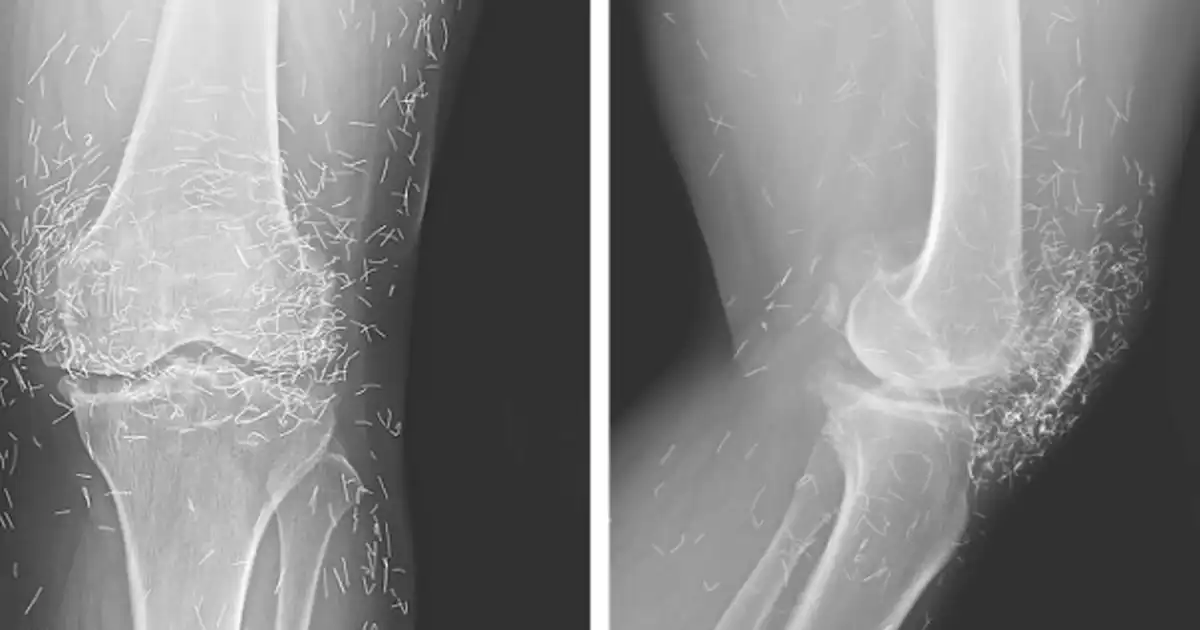

When a South Korean woman visited her doctor for knee pain, X-rays revealed something unexpected: tiny gold needles lodged inside her joints. The discovery traced back to an alternative arthritis treatment she had undergone years earlier.

According to a report in the New England Journal of Medicine, the woman underwent a version of acupuncture in which needles—believed to be made of gold—were intentionally left in her knees for continued stimulation.

Beyond infection, retained needles can complicate medical imaging. They may obscure X-ray results and, more seriously, make MRI scans dangerous. “Needles left in the body may move and damage an artery,” Guermazi said.